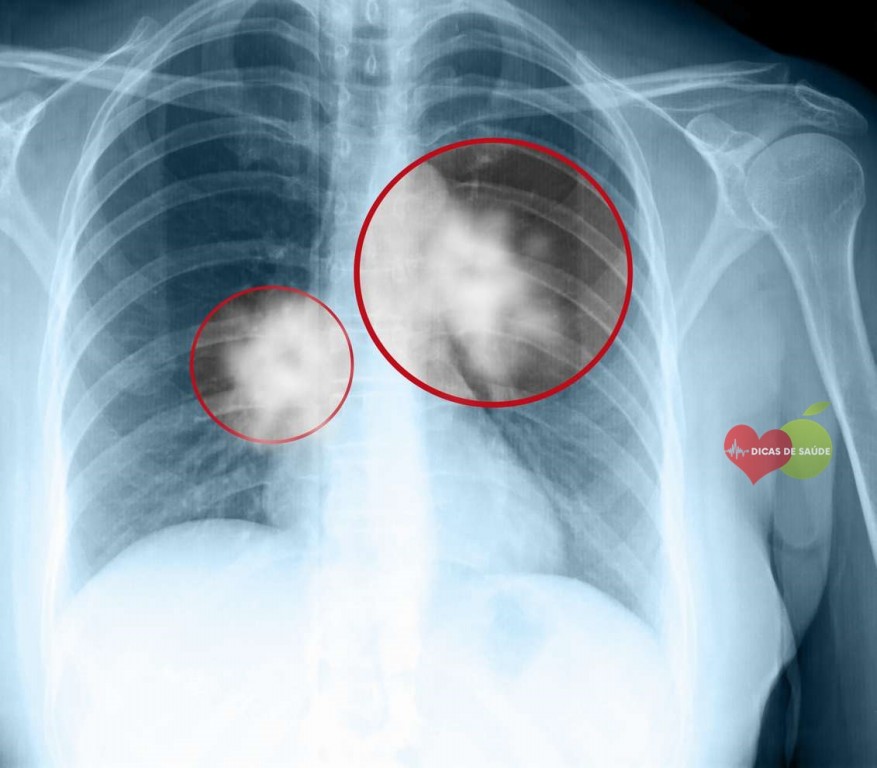

Mesotelioma Pleural: É o câncer no revestimento dos pulmões é o tipo mais comum de mesotelioma. Aqui estão os sintomas mais comuns: Os derrames pleurais são um dos sintomas mais importantes e definitivos da mesotelioma pleural. Um derrame pleural é um acúmulo de líquido entre a pleura parietal e da pleura visceral. Uma pesquisa aponta que cerca de 90% dos pacientes com mesotelioma pleural tiveram derrames pleurais. Falta de ar é o segundo sintoma mais comum relacionada com mesotelioma pleural. Alguns dos outros sintomas incluem o seguinte.

- Dor no peito / costelas durante a respiração

- Fadiga

- Tosse seca

- Suar

- Perda de peso sem motivo aparente